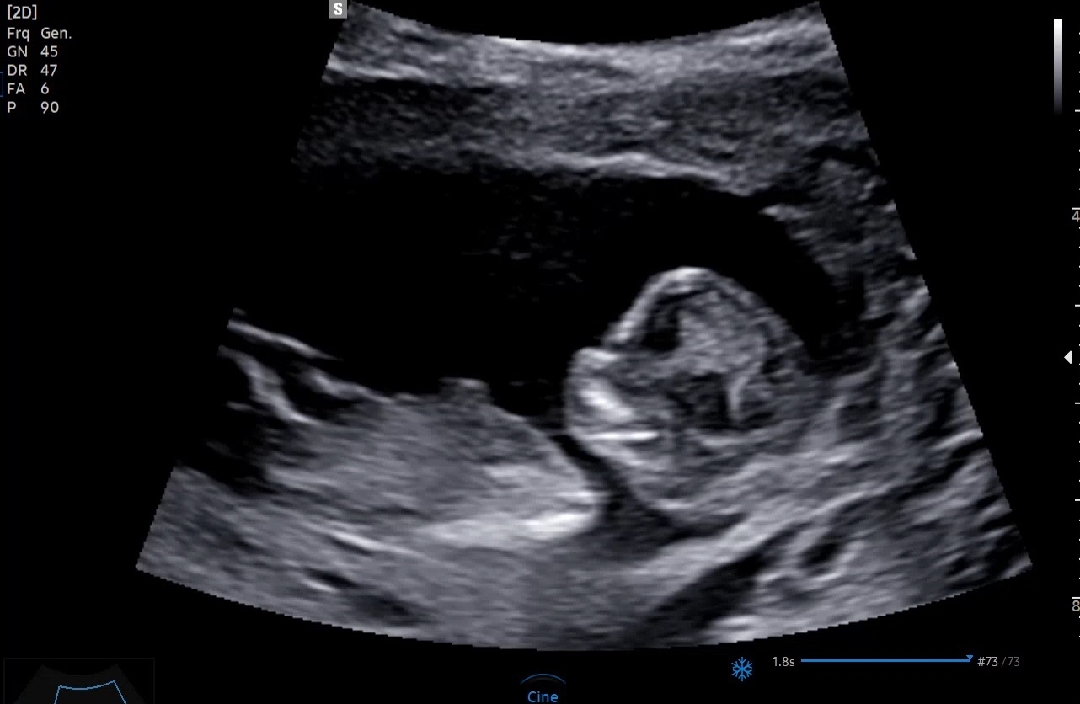

아들일까요? 딸일까요?

12주 인데요~~ 궁금해 미치겠어용ㅋㅋㅋ 아들일까요? 딸일까요?